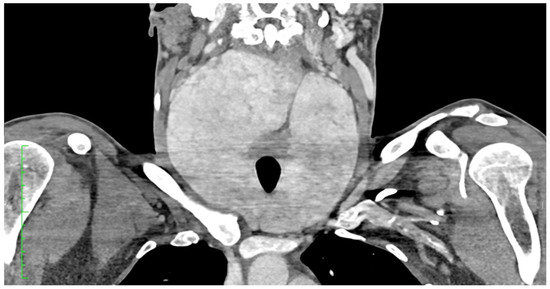

A Rare Case of Systemic Amyloidosis Involving the Thyroid in a Young Patient

by Oliwia Julia Kasprzak, Kamila Stępińska, Kaja Kiedrowska, Tomasz Błaszkowski, Aleksandra Kudrymska, Sylwia Sikora, Maciej Miernik and Maciej Romanowski

J. Clin. Med. 2025, 14(19), 6741; https://doi.org/10.3390/jcm14196741 - 24 Sep 2025

Thyroid amyloidosis is a rare condition associated with thyroid pathologies such as medullary carcinoma, papillary carcinoma, amyloid goitre, and benign lesions, with a clinically palpable goitre being exceptionally uncommon. As a result, many cases of benign thyroid enlargement caused by amyloid deposits remain [...] Read more.

Thyroid amyloidosis is a rare condition associated with thyroid pathologies such as medullary carcinoma, papillary carcinoma, amyloid goitre, and benign lesions, with a clinically palpable goitre being exceptionally uncommon. As a result, many cases of benign thyroid enlargement caused by amyloid deposits remain undiagnosed. A 28-year-old male patient noticed progressive neck circumference enlargement, voice alteration, decreased appetite, weight loss, dysphagia, fever, and night sweats. Fine-needle aspiration biopsy of the thyroid gland did not reveal the cause of the goitre. A total thyroidectomy was performed. Histopathological examination confirmed advanced thyroid amyloidosis. Full article

Show Figures

Figure 1